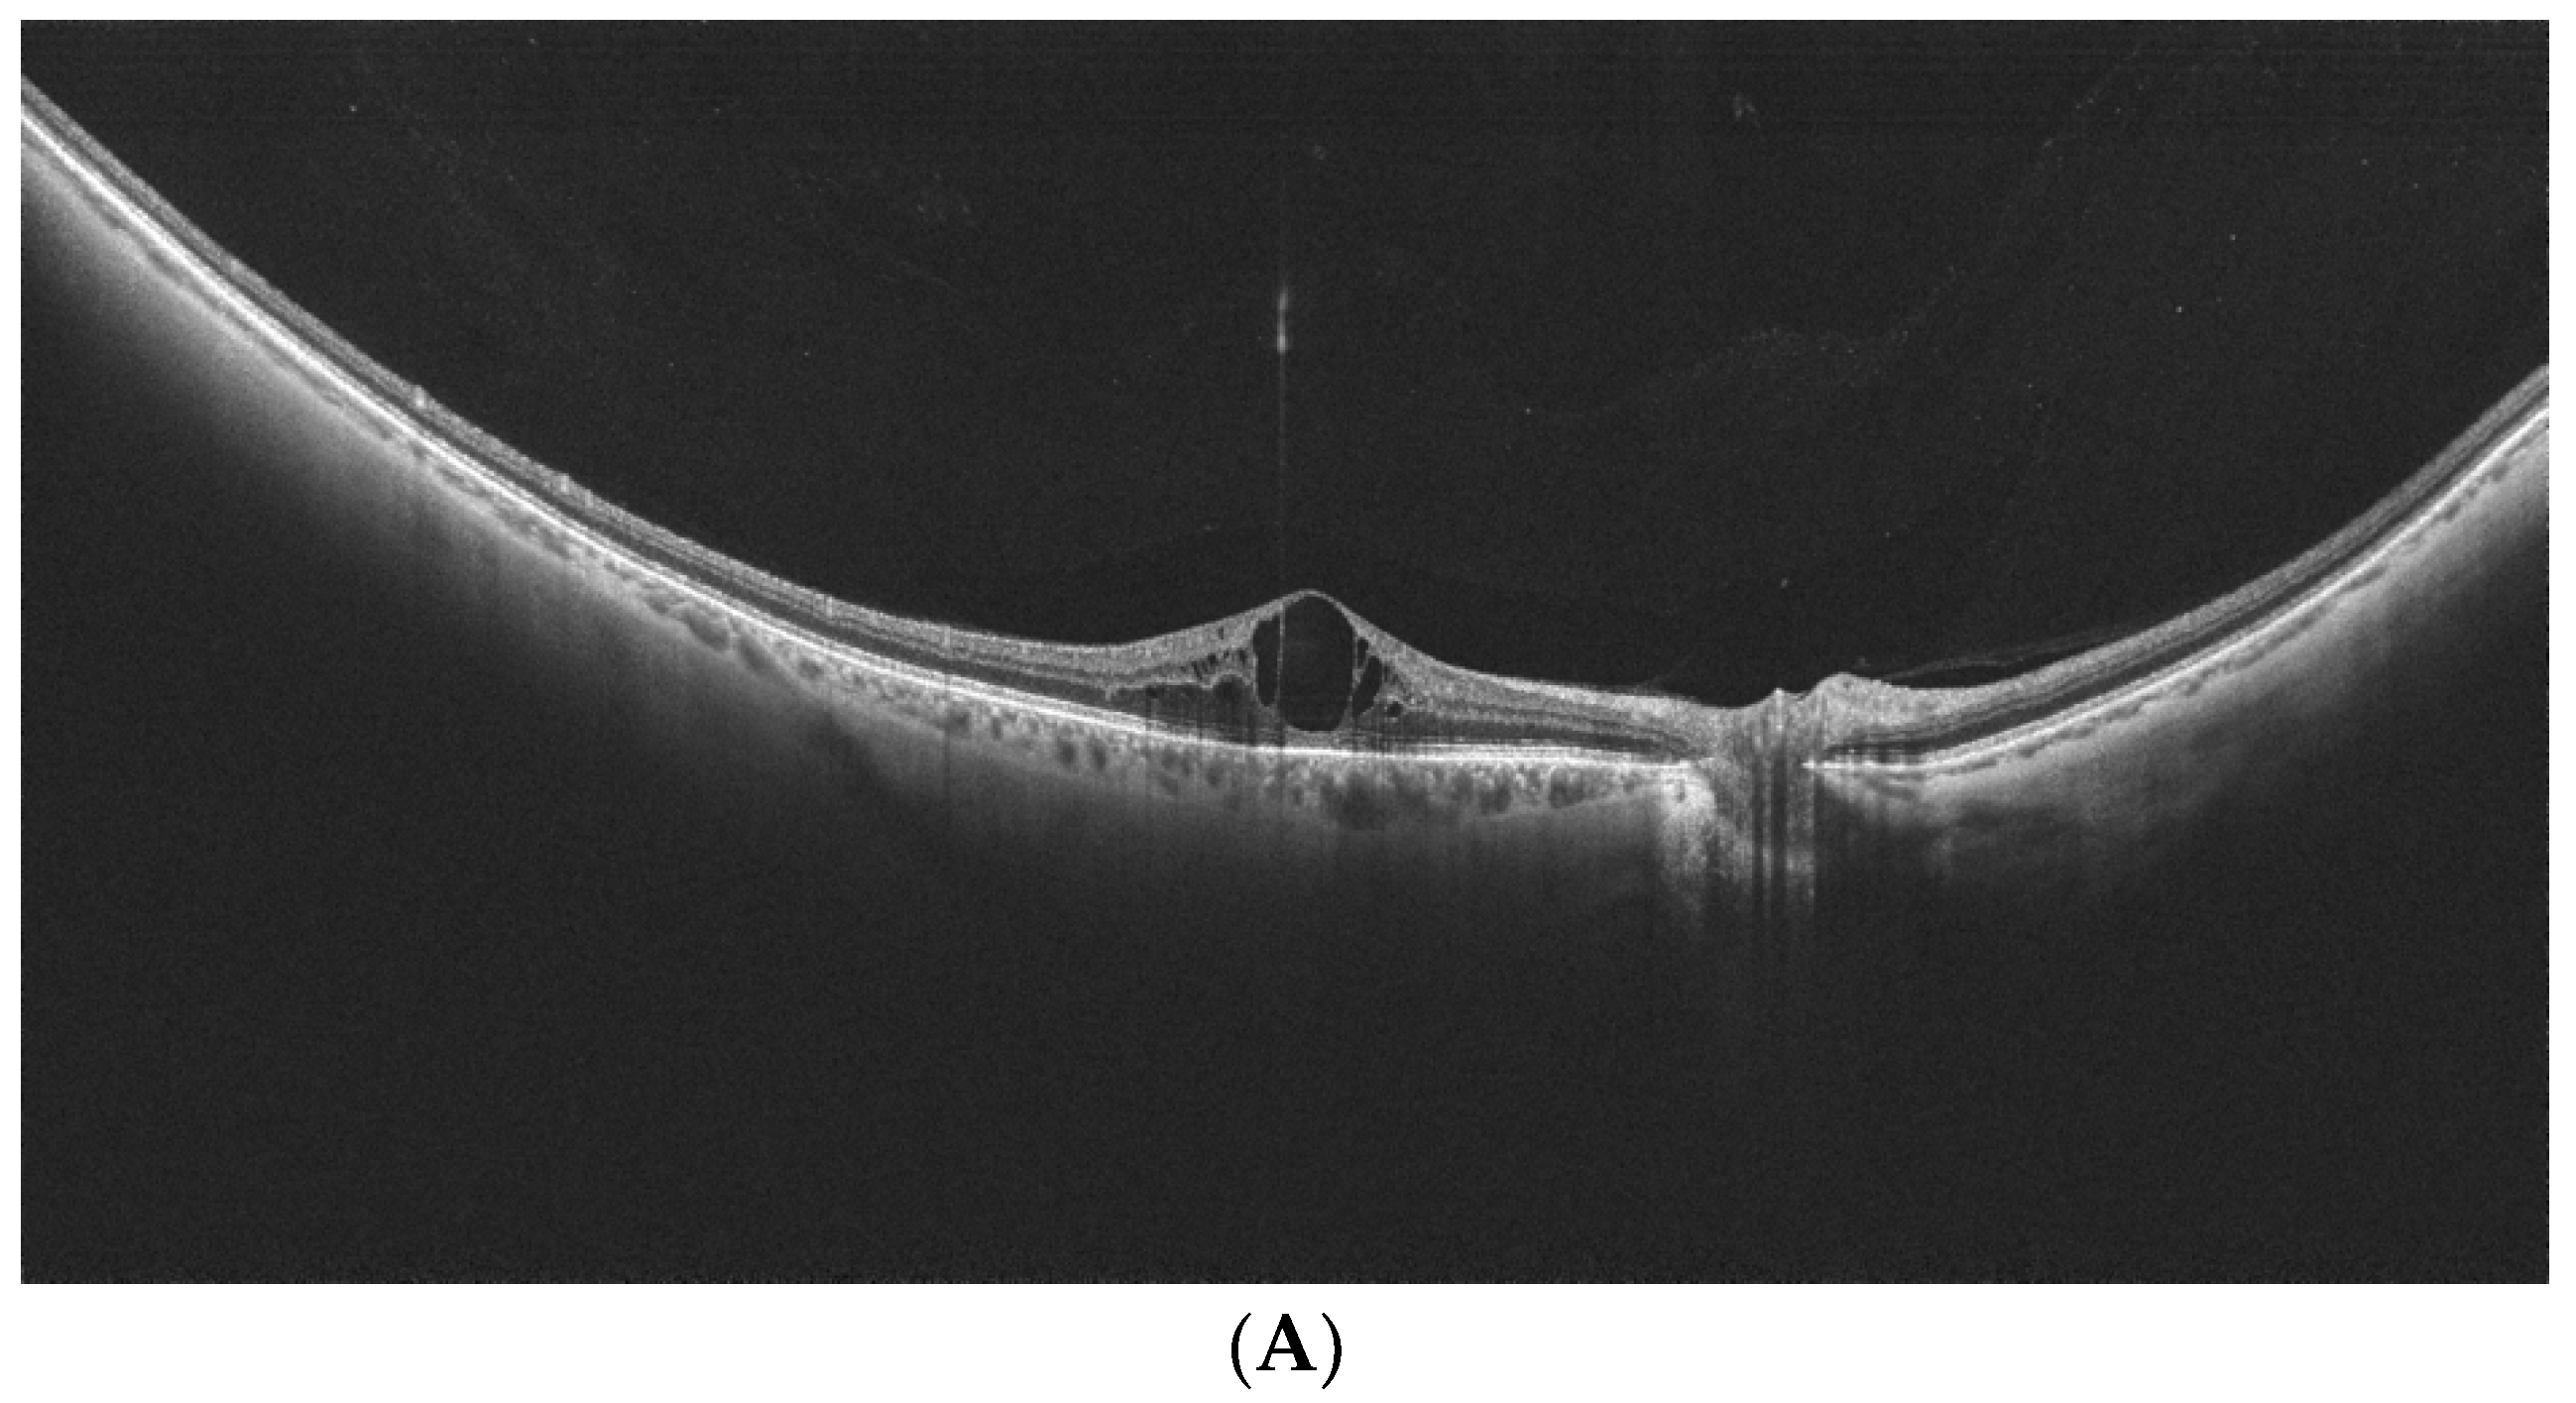

- Govetto, A.; Sebag, J.; Lucchini, S.; Ballabio, C.; Matteucci, M.; Ranno, S.; Carini, E.; Virgili, G.; Bacherini, D.; Radice, P. Imaging rhegmatogenous retinal lesions and peripheral vitreo-retinal interface with wide-field optical coherence tomography. Retina 2023, 44, 269–279. [Google Scholar] [CrossRef] [PubMed]

- Kurobe, R.; Hirano, Y.; Ogura, S.; Yasukawa, T.; Ogura, Y. Ultra-Widefield Swept-Source Optical Coherence Tomography Findings of Peripheral Retinal Degenerations and Breaks. Clin. Ophthalmol. 2021, 15, 4739–4745. [Google Scholar] [CrossRef] [PubMed]

- Stanga, P.E.; Pastor-Idoate, S.; Reinstein, U.; Vatas, P.; Patel, U.; Dubovy, S.; Reinstein, D.Z.; Zahavi, O. Navigated single-capture 3D and cross-sectional wide-field OCT of the mid and peripheral retina and vitreoretinal interface. Eur. J. Ophthalmol. 2022, 32, 1642–1651. [Google Scholar] [CrossRef] [PubMed]